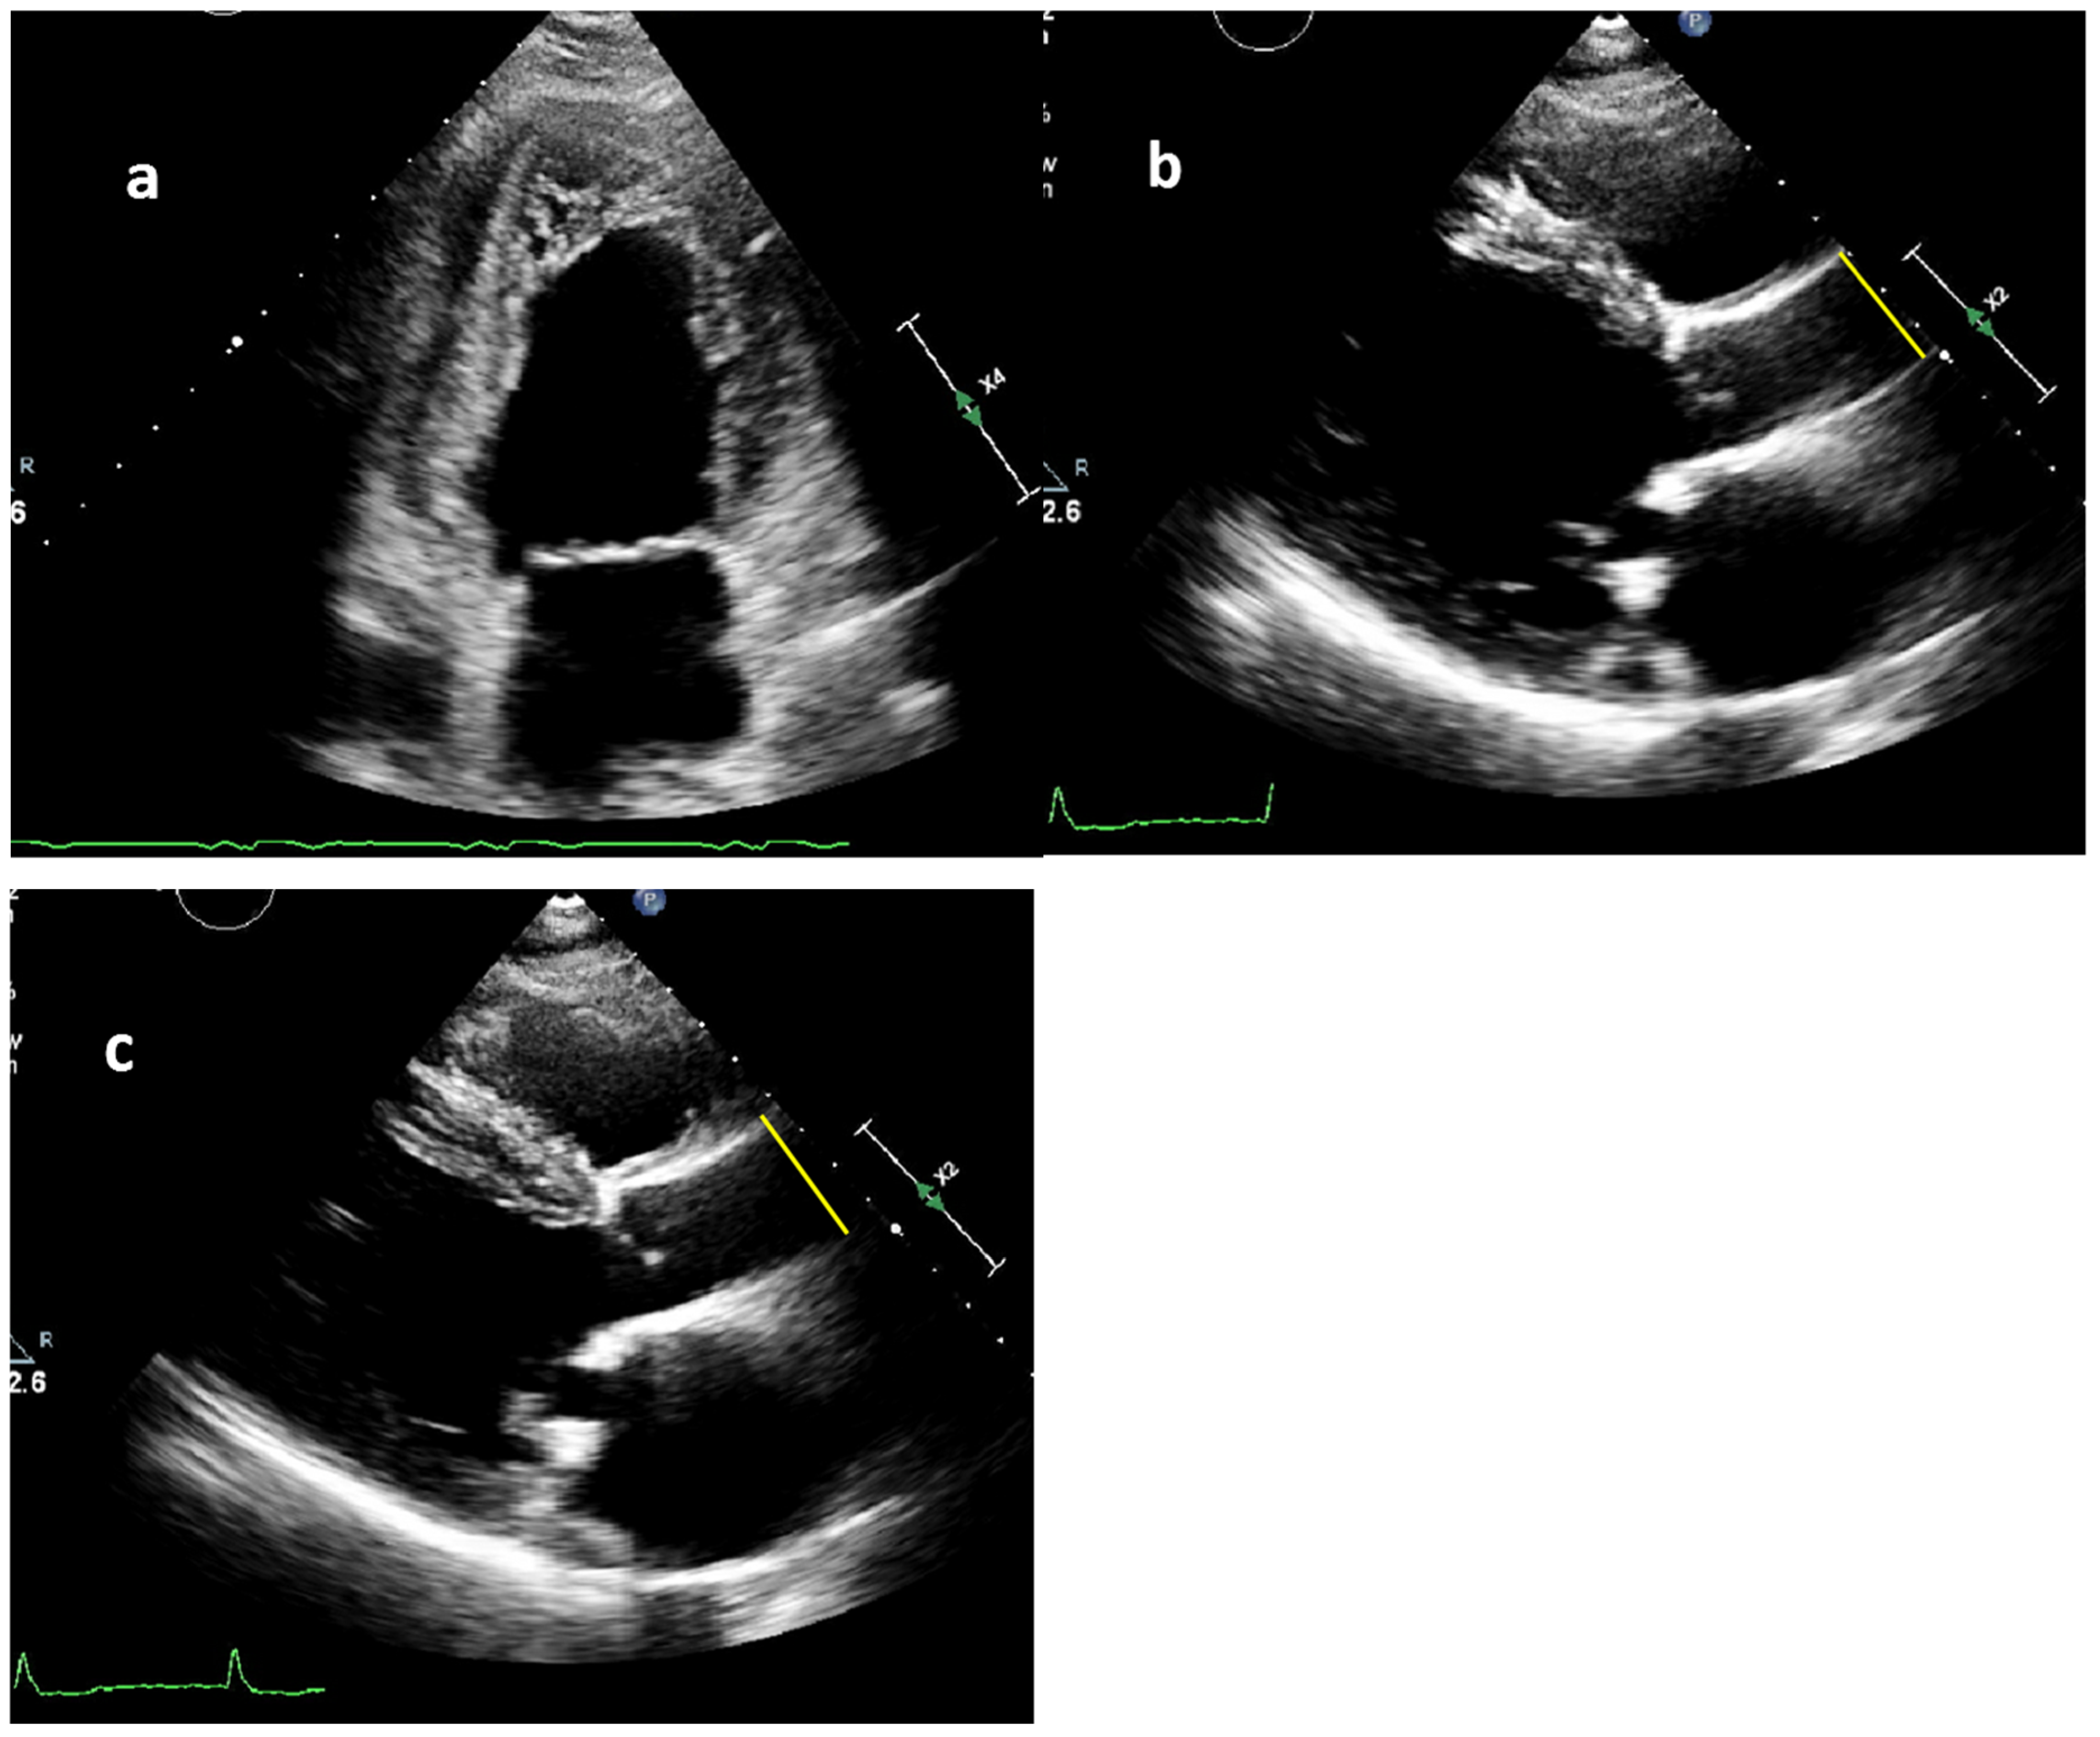

2.2. Measurement of Blood Pressure and Aortic Diameters

2.3. Aortic Stiffness Index

| Systolic ascending aortic diameter, mm | 30 ± 5 | 31 ± 5 | 0.883 |

| Diastolic ascending aortic diameter, mm | 28 ± 4 | 29 ± 5 | 0.483 |

| Aortic stiffness index # | 6.2 [4.8–7.7] | 7.0 [5.8–10.2] | 0.011 |